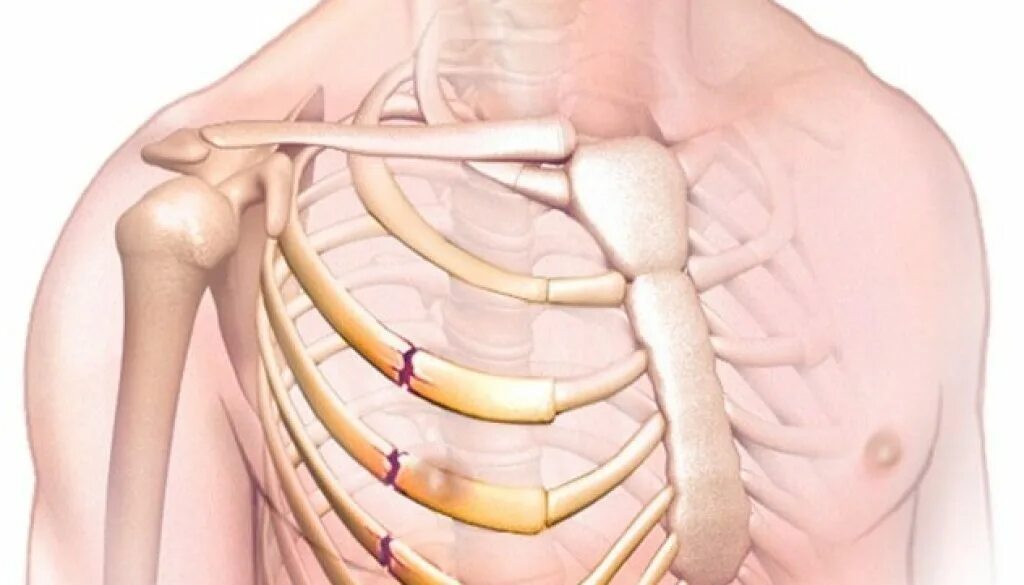

Множественные ребра